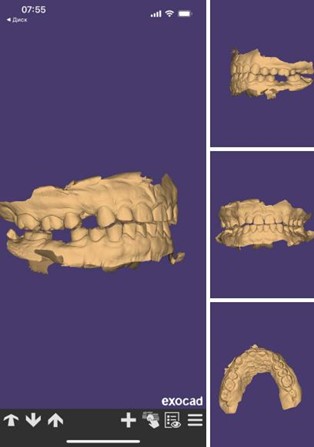

Очень круто, что под рукой всегда есть КТ и трёхмерные снимки, что направляющие для имплантации напечатаны на 3D-принтере. Можно посмотреть на трёхмерную модель своих будущих зубов и как они будут смотреться во рту. Модель могут скинуть в STL-формате. Это такие вещи, от которых я был просто в восторге!

С точки зрения самой работы было не очень трудно. Костная пластика приживается не всегда, но у Ивана она прижилась сразу и в полном объёме, импланты тоже сразу интегрировались. Некоторые зубы были слишком чувствительными, но это быстро проходило. После хирургии совсем уж сложных ситуаций не было. Иван вернулся, мы создали цифровой макет зубов, сделали сканирование в трёхмерной модели, которая называется Digital smile design, и тщательно насчитали будущую реставрацию в соответствии с запросами Ивана.

- STL-файлы в виде сканов верхней и нижней челюстей.

- Лицевую дугу — это специальное приспособление, которое передаёт положение и угол наклона верхней челюсти.

- Компьютерную томограмму.

- И полный фотопротокол.

Сканы обточенных зубов для временных коронок

Дальше мы отправили все эти данные технику. Он соединил их в единый проект и сделал, грубо говоря, цифровую модель головы пациента, с которой мы могли экспериментировать сколько влезет. Так что перед тем, как что-либо делать с реальным Иваном, мы спроектировали все действия в программе и проверили, как на это отреагирует его височно-нижнечелюстной сустав.

Цифровая модель зубов